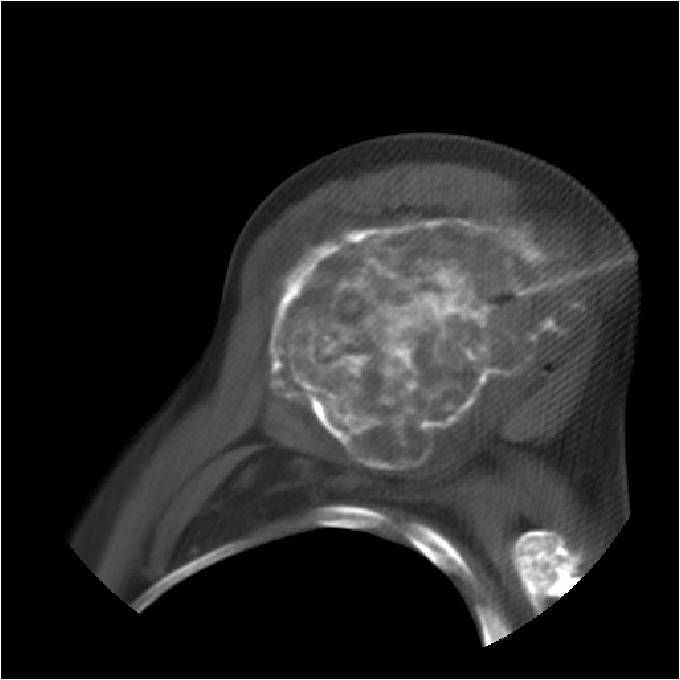

Radiographic Presentation

- Localized, radiolucent defect usually with punctate calcifications

- Calcifications are typical but not always present

- Matrix may demonstrate various degrees of calcification

- Calcifications are stippled, punctate, popcorn like calcifications and “Ring and Arc” calcifications

- Cartilage tumors grow in a lobular manner. The perimeters of the lobules undergo

- enchondral ossification that may calcify. If the entire perimeter of the lobule calcifies it appears

- radiographically as a “Ring”. If a portion of the perimeter of a lobule calcifies it forms an “Arc” on

- an X-ray.

- May be located centrally or eccentrically

- Most commonly found in metaphysis

Plain X-Ray:

- Geographic lytic lesion

- Central often metaphyseal in long bones

- Can be eccentric also

- Expansile remodeling with thinned cortex

- Chondroid matrix with calcifications in majority of tumors

- Approximately 20% have limited or no calcifications

- There should never be any cortical destruction nor a soft tissue component. If this exists then the tumor must be a chondrosarcoma.

- Endosteal scalloping and cortical expansion is acceptable for phalangeal tumors. In most benign long bone cartilage tumors there is minimal endosteal scalloping but there should be no cortical expansion nor thickening. There should be no cortical destruction and no soft tissue component associated with an enchondroma. Cortical destruction, periosteal thickening, cortical expansion and a soft tissue component indicates a chondrosarcoma of the long bone.

Ring and Arc Calcifications Minimal Endosteal Scalloping Cortex Intact No Soft Tissue Component No Periosteal Reaction

Ring and Arc Calcification No Endosteal Scalloping

Metaphyseal Tumor Heavy Calcifications Ring and Arc Pattern of Calcifications Minimal Endosteal Scalloping No Cortical Destruction No Periosteal Reaction No Cortical Destruction No Soft Tissue Component